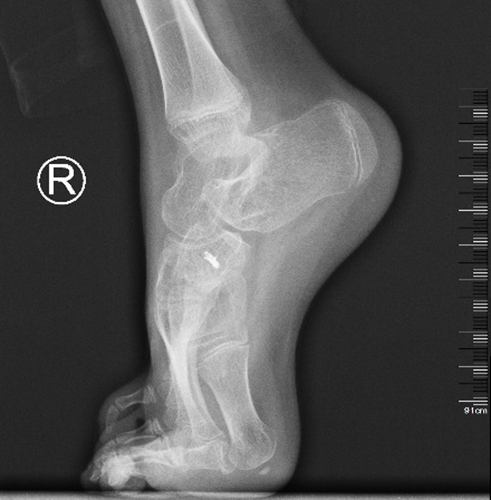

近日,青島婦女兒童醫(yī)院康復(fù)門診收治了兩例踝關(guān)節(jié)痙攣的患兒,5歲的女孩彤彤(化名)和12歲的男孩鵬鵬(化名)。接診醫(yī)生發(fā)現(xiàn)兩名患兒雖然病因不同,卻都造成了不同程度的踝關(guān)節(jié)攣縮癥狀:彤彤因一次意外摔傷導(dǎo)致右脛骨骨折,手術(shù)后長期臥床制動,肌肉和關(guān)節(jié)周圍的肌肉萎縮,從而導(dǎo)致踝關(guān)節(jié)攣縮;鵬鵬因左小腿血管瘤疼痛而長期踮腳走路,長時間的不正確走姿,出現(xiàn)繼發(fā)踝關(guān)節(jié)攣縮。

踝關(guān)節(jié)是人體主要的負重結(jié)構(gòu),如不及時治療,將影響患兒步態(tài),出現(xiàn)步行穩(wěn)定性下降,走路時容易摔倒,影響跑、跳等高級運動能力,嚴重畸形時甚至不能繼續(xù)行走。

康復(fù)團隊針對患兒踝關(guān)節(jié)攣縮表現(xiàn),采取“系列石膏+肌肉激活技術(shù)+運動和姿勢控制管理”的治療方案。其中,石膏固定療法根據(jù)患兒體征定做下肢支具,改造鞋底以矯正下肢不等長,并通過持續(xù)肌肉牽伸和關(guān)節(jié)塑型,循序漸進的改善攣縮、擴大關(guān)節(jié)活動范圍。牽伸、關(guān)節(jié)松動術(shù)等手法治療與主動、被動運動療法相結(jié)合,可以恢復(fù)軟組織的延展性與彈性,幫助患兒擴大關(guān)節(jié)活動度,重新激活主動肌,學(xué)會對稱性、主動性姿勢控制和力線調(diào)直,促進患肢使用及功能重建。

經(jīng)過一段時間的康復(fù)治療,兩個孩子從外觀到功能都有了很大進步,彤彤可以腳跟著地保持蹲位了;鵬鵬不僅腳后跟可以落地,踮腳也明顯減輕。經(jīng)過持續(xù)干預(yù)治療,這些癥狀將得到進一步改善。